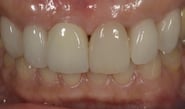

Simplified Microscopic Implant surgical Lifelike Esthetics を略した手術名で、米国カルフォルニア州サンタバーバラで歯周病専門医として開業されていた、 Dr. Dennis Shanelec(故人)が考案した治療法です。抜歯した直後に仮歯を入れることによって,歯を取り巻く骨(硬組織)や歯肉(軟組織)の状態を維持できる非常に優れた方法です。しかし、手術としての難易度は非常に高いレベルに位置づけられます。

抜歯した直後にインプラントを埋入し、仮の歯を作製、唇側の骨のボリュームを保つために人工骨と結合組織を同時に移植する非常に優れた方法です。